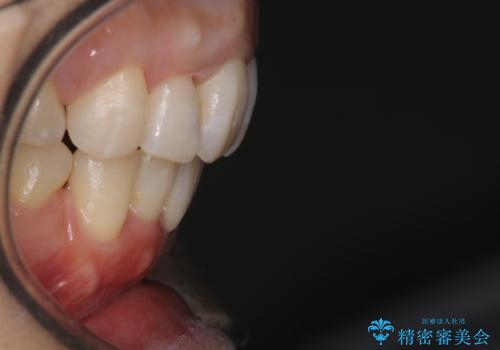

上顎の前歯は前方に傾斜して、下顎の前歯は強いガタガタが見られました。

前から4番目の歯を上下左右合計2本抜歯して、歯並びを整える計画としました。